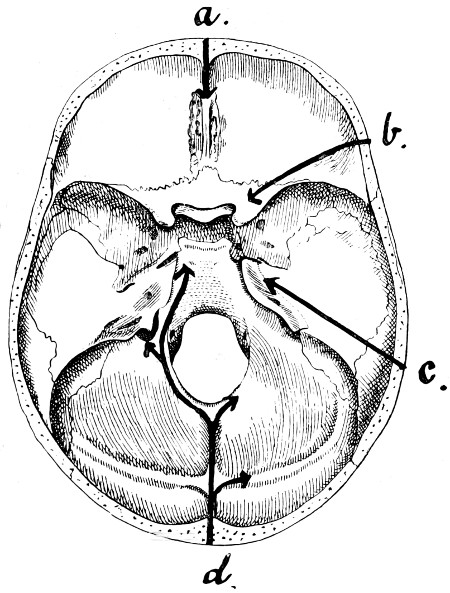

29 A and B. The base of the skull and the base as seen on transillumination 70, 71

30. Plan of the base of the skull 77

31. To illustrate the relation of basic fractures to cranial nerves 81

32-37. The lines pursued by basic fractures 83-8